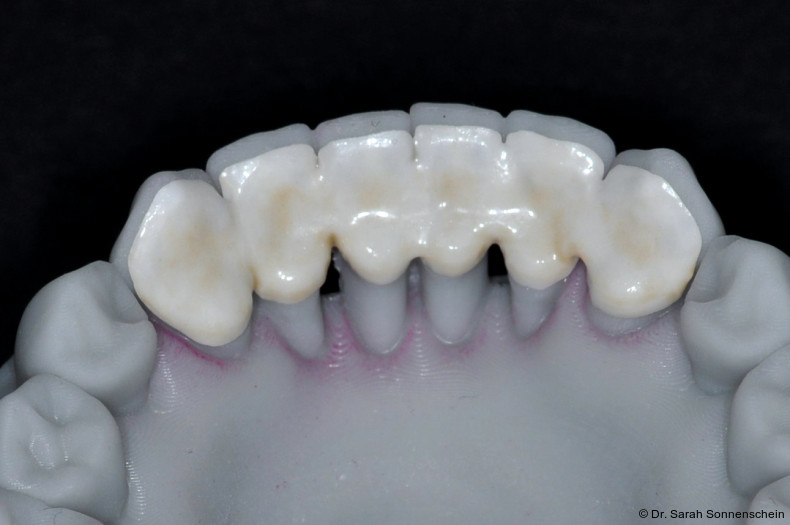

In den letzten Jahren hat sich auch die Zahnmedizin zunehmend digitalisiert. Mit Intraoralscannern können hochpräzise dreidimensionale Modelle der Kiefer und Zähne erstellt werden, auch vom parodontal geschädigten Gebiss.18 Es gehört heute zum zahnmedizinischen Standard, dass auf Basis von digitalen 3D-Modellen metallfreier zahnfarbener Zahnersatz wie Einzelzahnkronen oder Brücken aus Zirkoniumoxid (ZrO2) im subtraktiven Fräsverfahren hergestellt werden. Eine völlig neue Methode zur Herstellung von Zahnersatz oder zahnmedizinischen Hilfsteilen eröffnet sich mit der Möglichkeit, ZrO2 in speziellen 3D-Druckern erstellen zu können. Ein Vorteil gedruckter Konstruktionen liegt darin, dass die geometrischen Möglichkeiten nicht durch die Anzahl der Fräsachsen beschränkt ist. In einer aktuellen experimentellen Studie wurde gezeigt, dass bei der adhäsiven Zementierung von gedruckten ZrO2-Restaurationen eine ähnlich hohe Haftkraft erzielt werden kann, wie für gefräste Restaurationen.19 Durch die Anwendung dieser neuen Technik könnte es möglich sein, in Zukunft gut haftende, bruchstabile und ästhetisch hochwertige zahnfarbene Schienen im Labor herzustellen. Erste Vorversuche zu diesem Vorgehen (Abb. 4) zeigen vielversprechende Ergebnisse, und es ist mit Spannung zu erwarten, ob und wie sich diese Möglichkeit weiter entwickeln wird.

Die Schienung parodontal geschädigter und stark gelockerter Unterkieferfrontzähne stellt in vielen Fällen eine mittel- bis langfristige Alternative zur Extraktion dar. Bei regelmäßiger UPT belegen Studien eine hohe parodontale Langzeitstabilität geschienter Zähne. Schienungsbrüche kommen zwar häufig vor, sind in der Unterkieferfront aber deutlich seltener und leicht reparabel. Bei Schienung vor subgingivaler Instrumentierung zeigt sich eine Tendenz zu besseren Ergebnissen der Parodontitistherapie und eine schnellere Verbesserung der MLQ. Die Schienung nach subgingivaler Instrumentierung bietet den Vorteil, dass ein möglicher Rückgang der Zahnlockerung feststellbar ist. Ist ein Zahn innerhalb der Verblockung nicht erhaltungsfähig, kann er nach Extraktion als adhäsives Pontic in den Verbund reintegriert werden. In einigen Fällen ist es auch möglich, die Wurzel oral abzutrennen und einfach die Zahnkrone im Verblockungsverbund stehen zu lassen. Besonders bei Risikopatienten kann dieses Vorgehen sinnvoll sein.Die hohe Frakturanfälligkeit macht eine Weiterentwicklung im Prozess der Schienungseinbringung, der verwendeten Materialien und des Konstruktionsdesigns dringend erforderlich, wobei erste Versuche mit 3D-gedruckten Schienen vielversprechend erscheinen.Die Verfasserin des Textes pflegt keinerlei wirtschaftliche oder persönliche Verbindung zu den genannten Unternehmen.